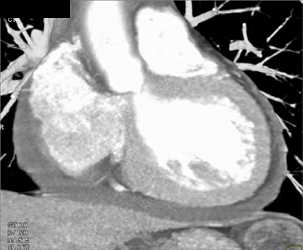

Type A Dissection